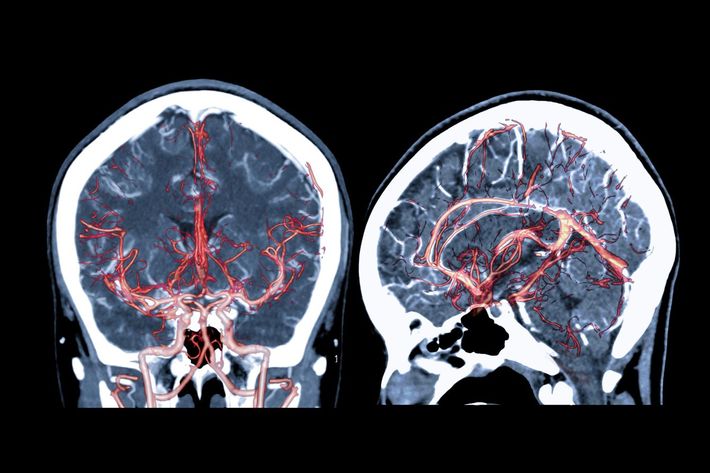

「裸のママが泣き叫んでる」高3息子からのSOS…"健診オールA"でも大量に出血した脳画像を見た夫の絶望

※写真はイメージです